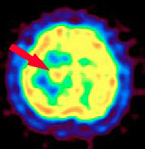

核医学検査(RI検査)ではIMP(イノシン酸)という物質に放射性物質を結合させた123I-IMPを注射すると悪性リンパ腫に結合します。通常の脳腫瘍には結合しないので、この検査で結合が見られる場合、脳悪性リンパ腫である確率はかなり高くなります。(右図矢印)